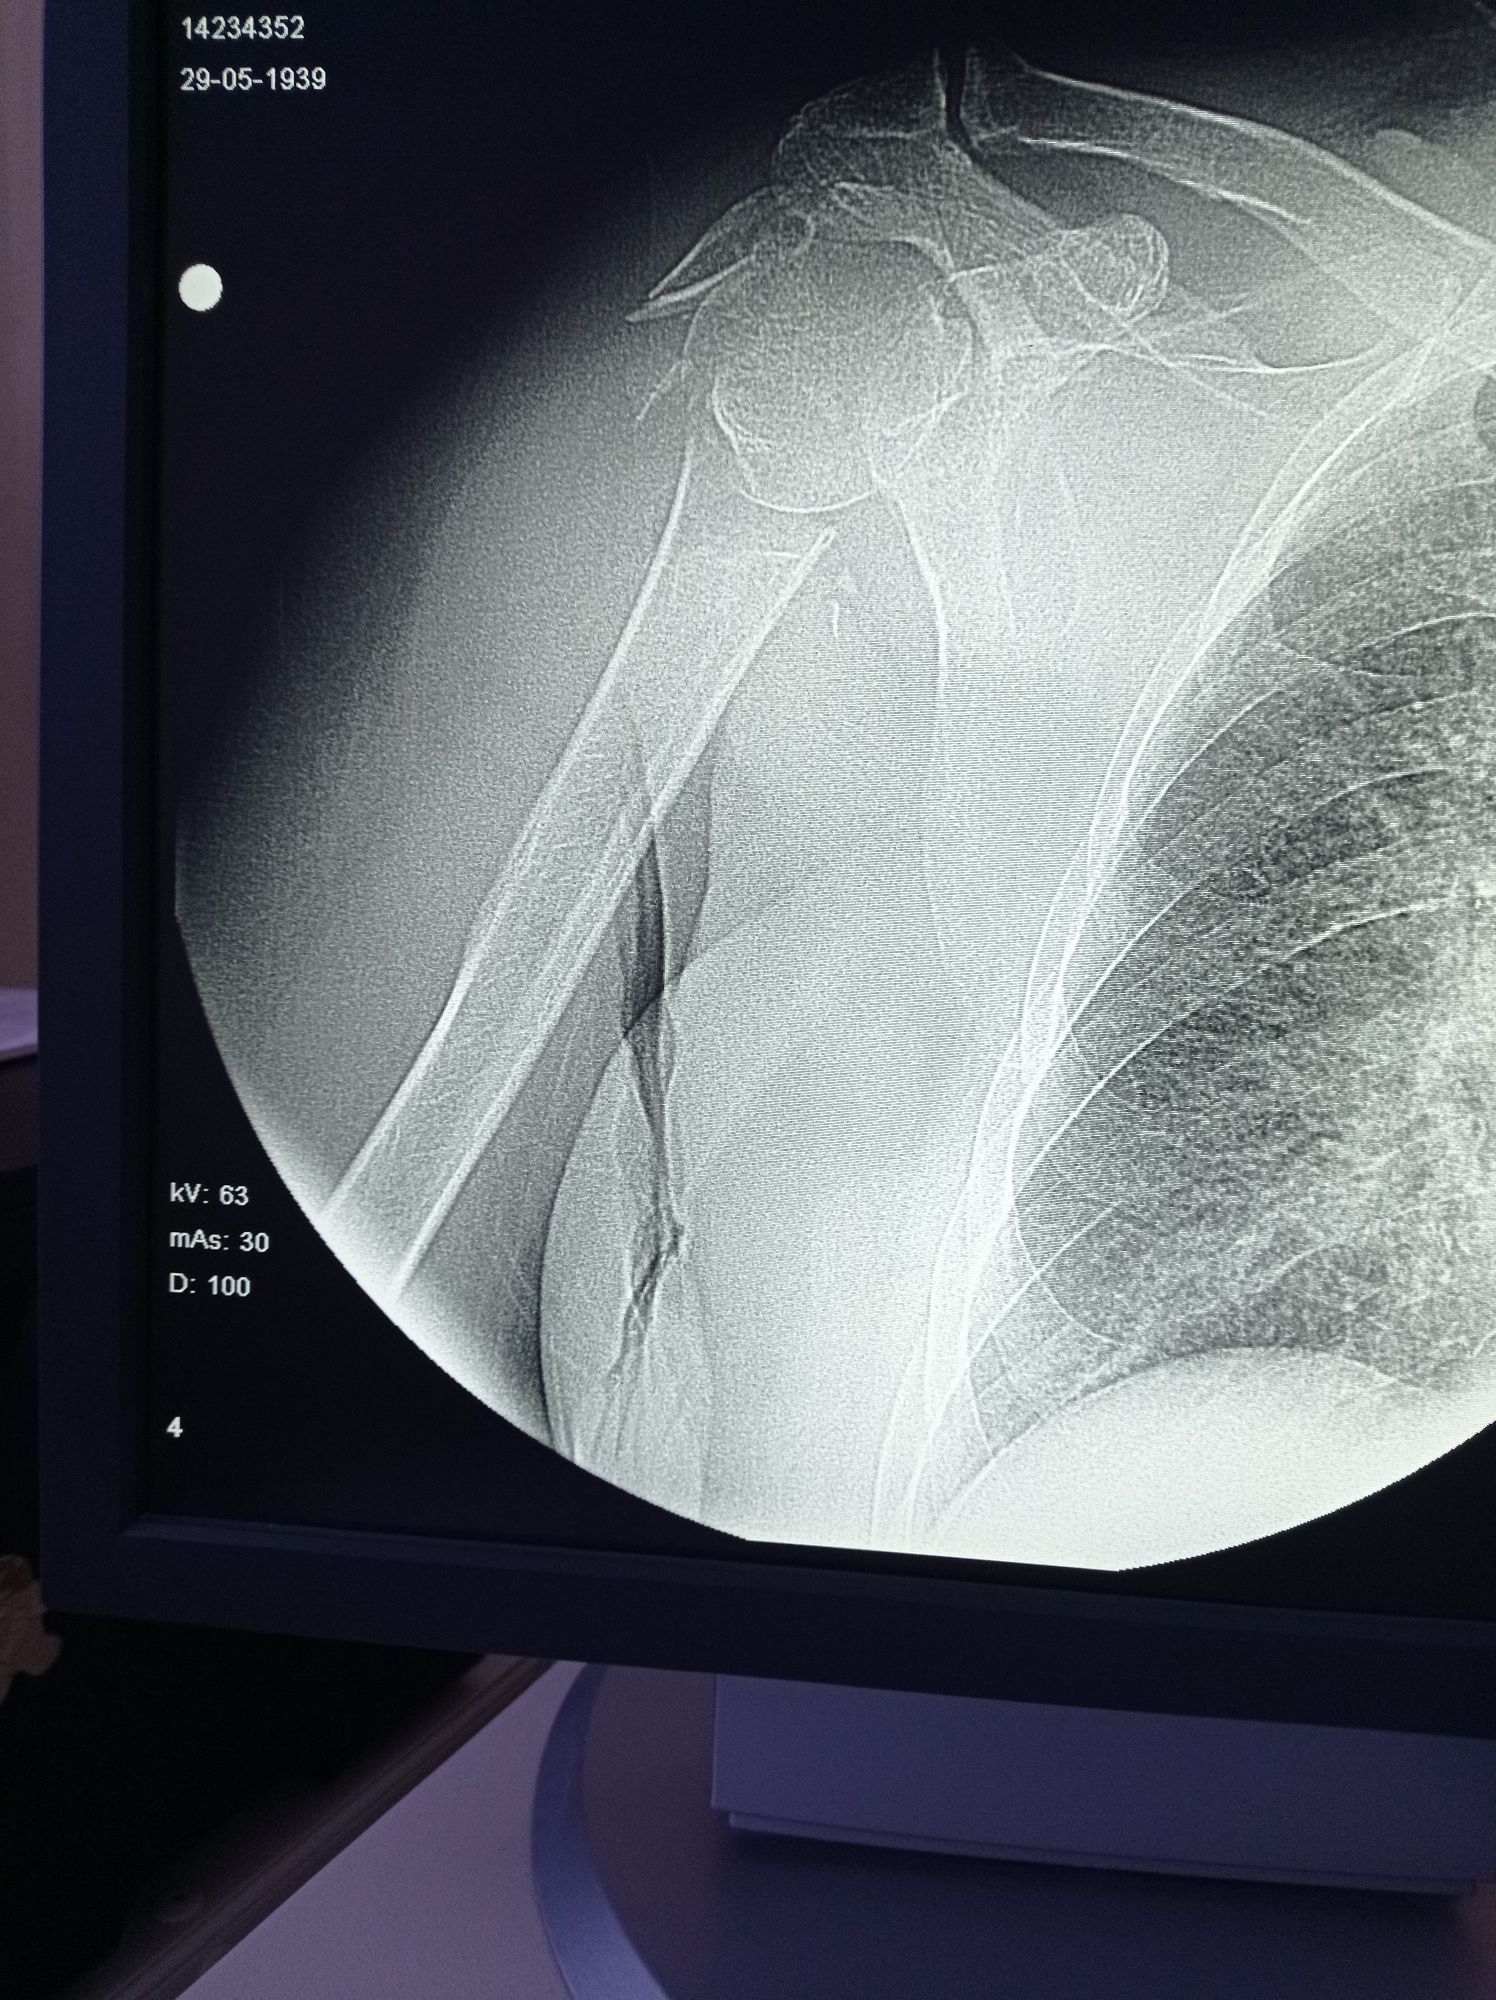

Dr.Murad

humerus head fracture

Trauma

Xray

Fracture